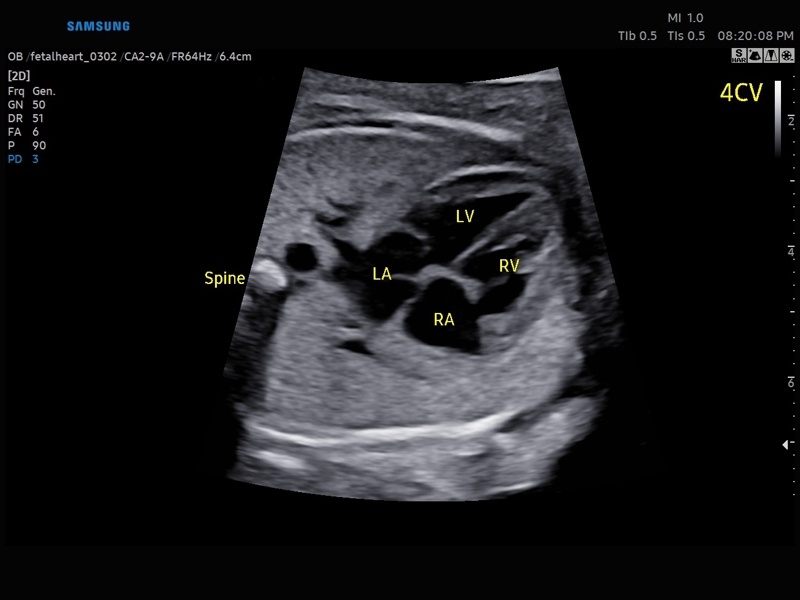

• Сердце плода:измерения в В-режиме (отношение площади сердца и грудной клетки), измерения в М-режиме (толщина межжелудочковой перегородки в диастолу, конечнодиастолический размер левого желудочка, толщина задней стенки левого желудочка в диастолу, толщина межжелудочковой перегородки в систолу, размер левого желудочка в систолу, толщина задней стенки левого желудочка в систолу, внутренний размер правого желудочка в диастолу), измерения в режиме спектрального допплера (легочный ствол, артериальный проток, нижняя полая вена, венозный проток, восходящая аорта, нисходящая аорта, трансмитральный кровоток, митральная регургитация, трикуспидальный кровоток, трикуспидальная регургитация, индекс преднагрузки, ЧСС).

• МодульSTIC- объемная динамическая визуализация сердца плода.